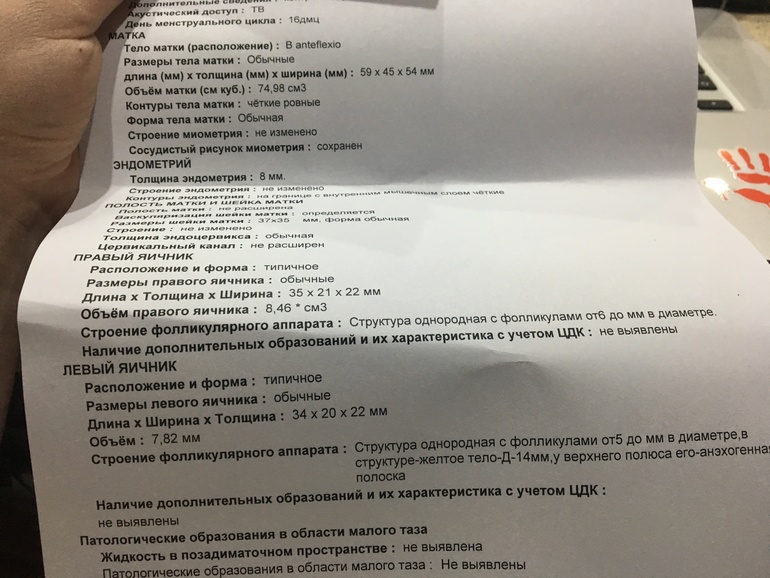

27 уже было жт а вокруг него жидкость врач сказала овуляция только только

я сама жт видела щас фото пришлю